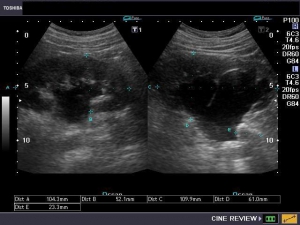

Η διάγνωση της νόσου γίνεται υπερηχογραφικά. Η διεύρυνση της νεφρικής πυέλου φαίνεται ικανοποιητικά στον υπερηχοτομογραφικό έλεγχο, κατά τον οποίο μετρώνται οι διαστάσεις τόσο της νεφρικής πυέλου και τον νεφρού, όσο και των ουρητήρων (αν αυτό είναι εφικτό). Ωστόσο, στις περιπτώσεις που το πρόβλημα είναι συγγενές, μπορεί να εντοπιστεί και προγεννητικά με το προγεννητικό υπερηχογράφημα, όπως αναφέρεται πιο πάνω.

Υπάρχουν πολλές μέθοδοι υπολογισμού της βαρύτητας της υδρονέφρωσης και διάφορα συστήματα ταξινόμησής της, ανάλογα με το μέγεθος της πυέλου, των ουρητήρων, κλπ.